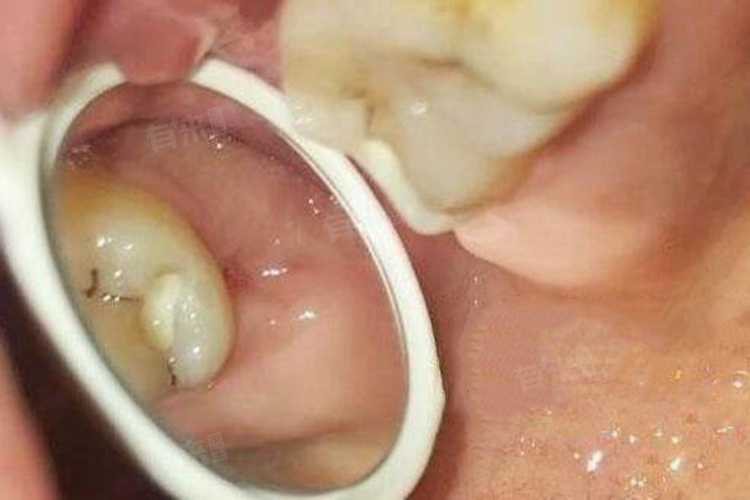

拔完牙后疼痛持续的时间因人而异,取决于拔牙的复杂程度、个人身体状况和术后护理情况等多种因素,一般拔牙后的疼痛持续时间范围在24小时到7天范围内。